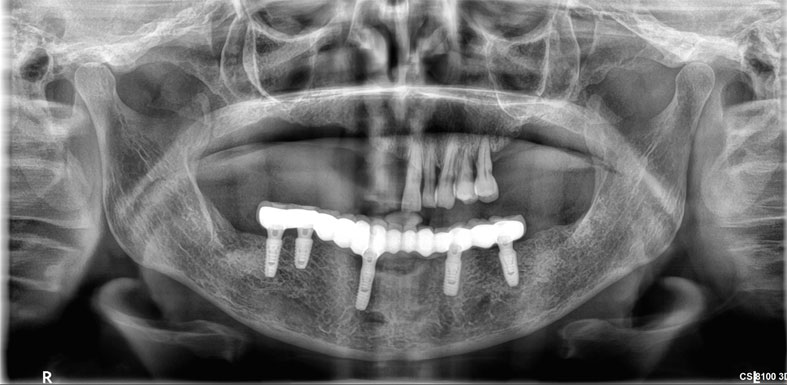

Dental Implants

Dental implants are artificial tooth roots use to replace decayed or missing teeth. They are a popular and effective long-term solution, dental implants are placed into the jawbone, providing a stability for replacement teeth.